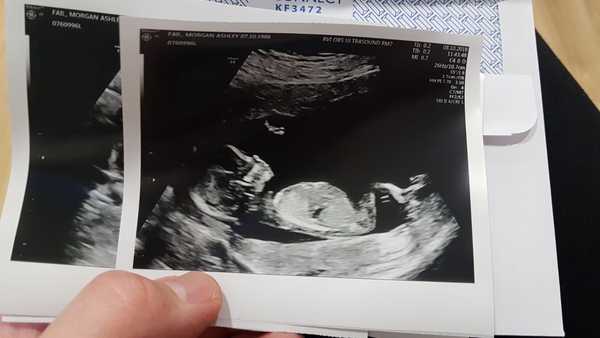

I've been a real chicken and been a lurker so far. In my last pregnancy, I joined a club and then had to leave after bad news at 12 weeks. Didn't want to do that again this time so waited for the scan. It was all good. Looking just as it should!

Due April 17th.

I'm in love with this little face!

wit, migmog and shared, congrats on the lovely pics! Mine was today too, i was really not expecting all the movement: wiggling, twisting, waving and opening mouth like he was saying something! It was hilarious! They had a new machine so the sonographer was taking some extra time playing with the settings which was great as we had more time to sit mesmerized watching the screen! Saying that it was a new machine, the pic is not as clear as others but will try and attach.

That's awesome 5starlight great that you got so much time watching baby, and a lovely pic!